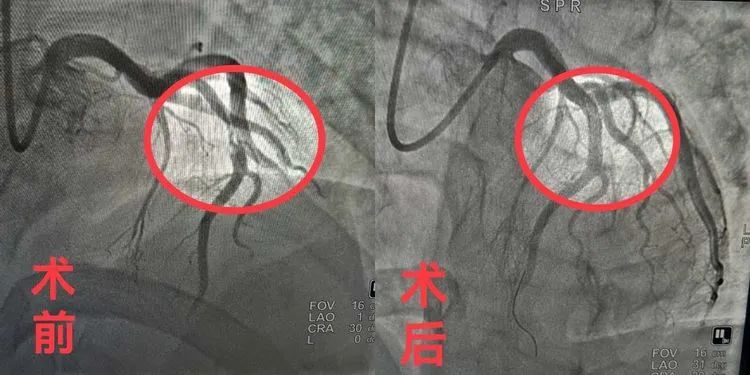

在进行急诊检查时候于先生心电图显示广泛前壁ST段弓背样抬高,被诊断为急性广泛前壁心肌梗死。在广济医院胸痛救治单元的统筹下,检查的同时导管室已经及时启动,为于先生第一时间建立绿色通道进行心血管介入治疗术。随后于先生被第一时间送入导管室,集团心内医疗中心院长李枫带领广济医院心内科团队立即为其手术,李院长熟练入路,见患者LAD(冠状动脉左前降支)中段90%狭窄伴血栓形成,李院长和团队果断对其LAD(冠状动脉左前降支)进行血栓抽吸,并顺利行支架植入术。支架植入后,患者的血管狭窄瞬间解除,于先生安返病房。

术后,广济医院心内科主任桂陈介绍,于先生这次十分凶险,当时他的LAD(冠状动脉左前降支)堵塞达90%且有血栓形成,再晚一点后果都不堪设想。幸运的是我们非常及时的为他急诊行冠状动脉造影+支架植入术,快速开通血管,以最快的速度恢复了他的心肌再灌注,最大限度的拯救了濒临死亡的心肌细胞,使他成功转危为安,现在他恢复良好很快就要出院返家了。”桂主任表示,这次的成功救治得益于医院集团胸痛中心先进理念和过硬技术的成功推广。